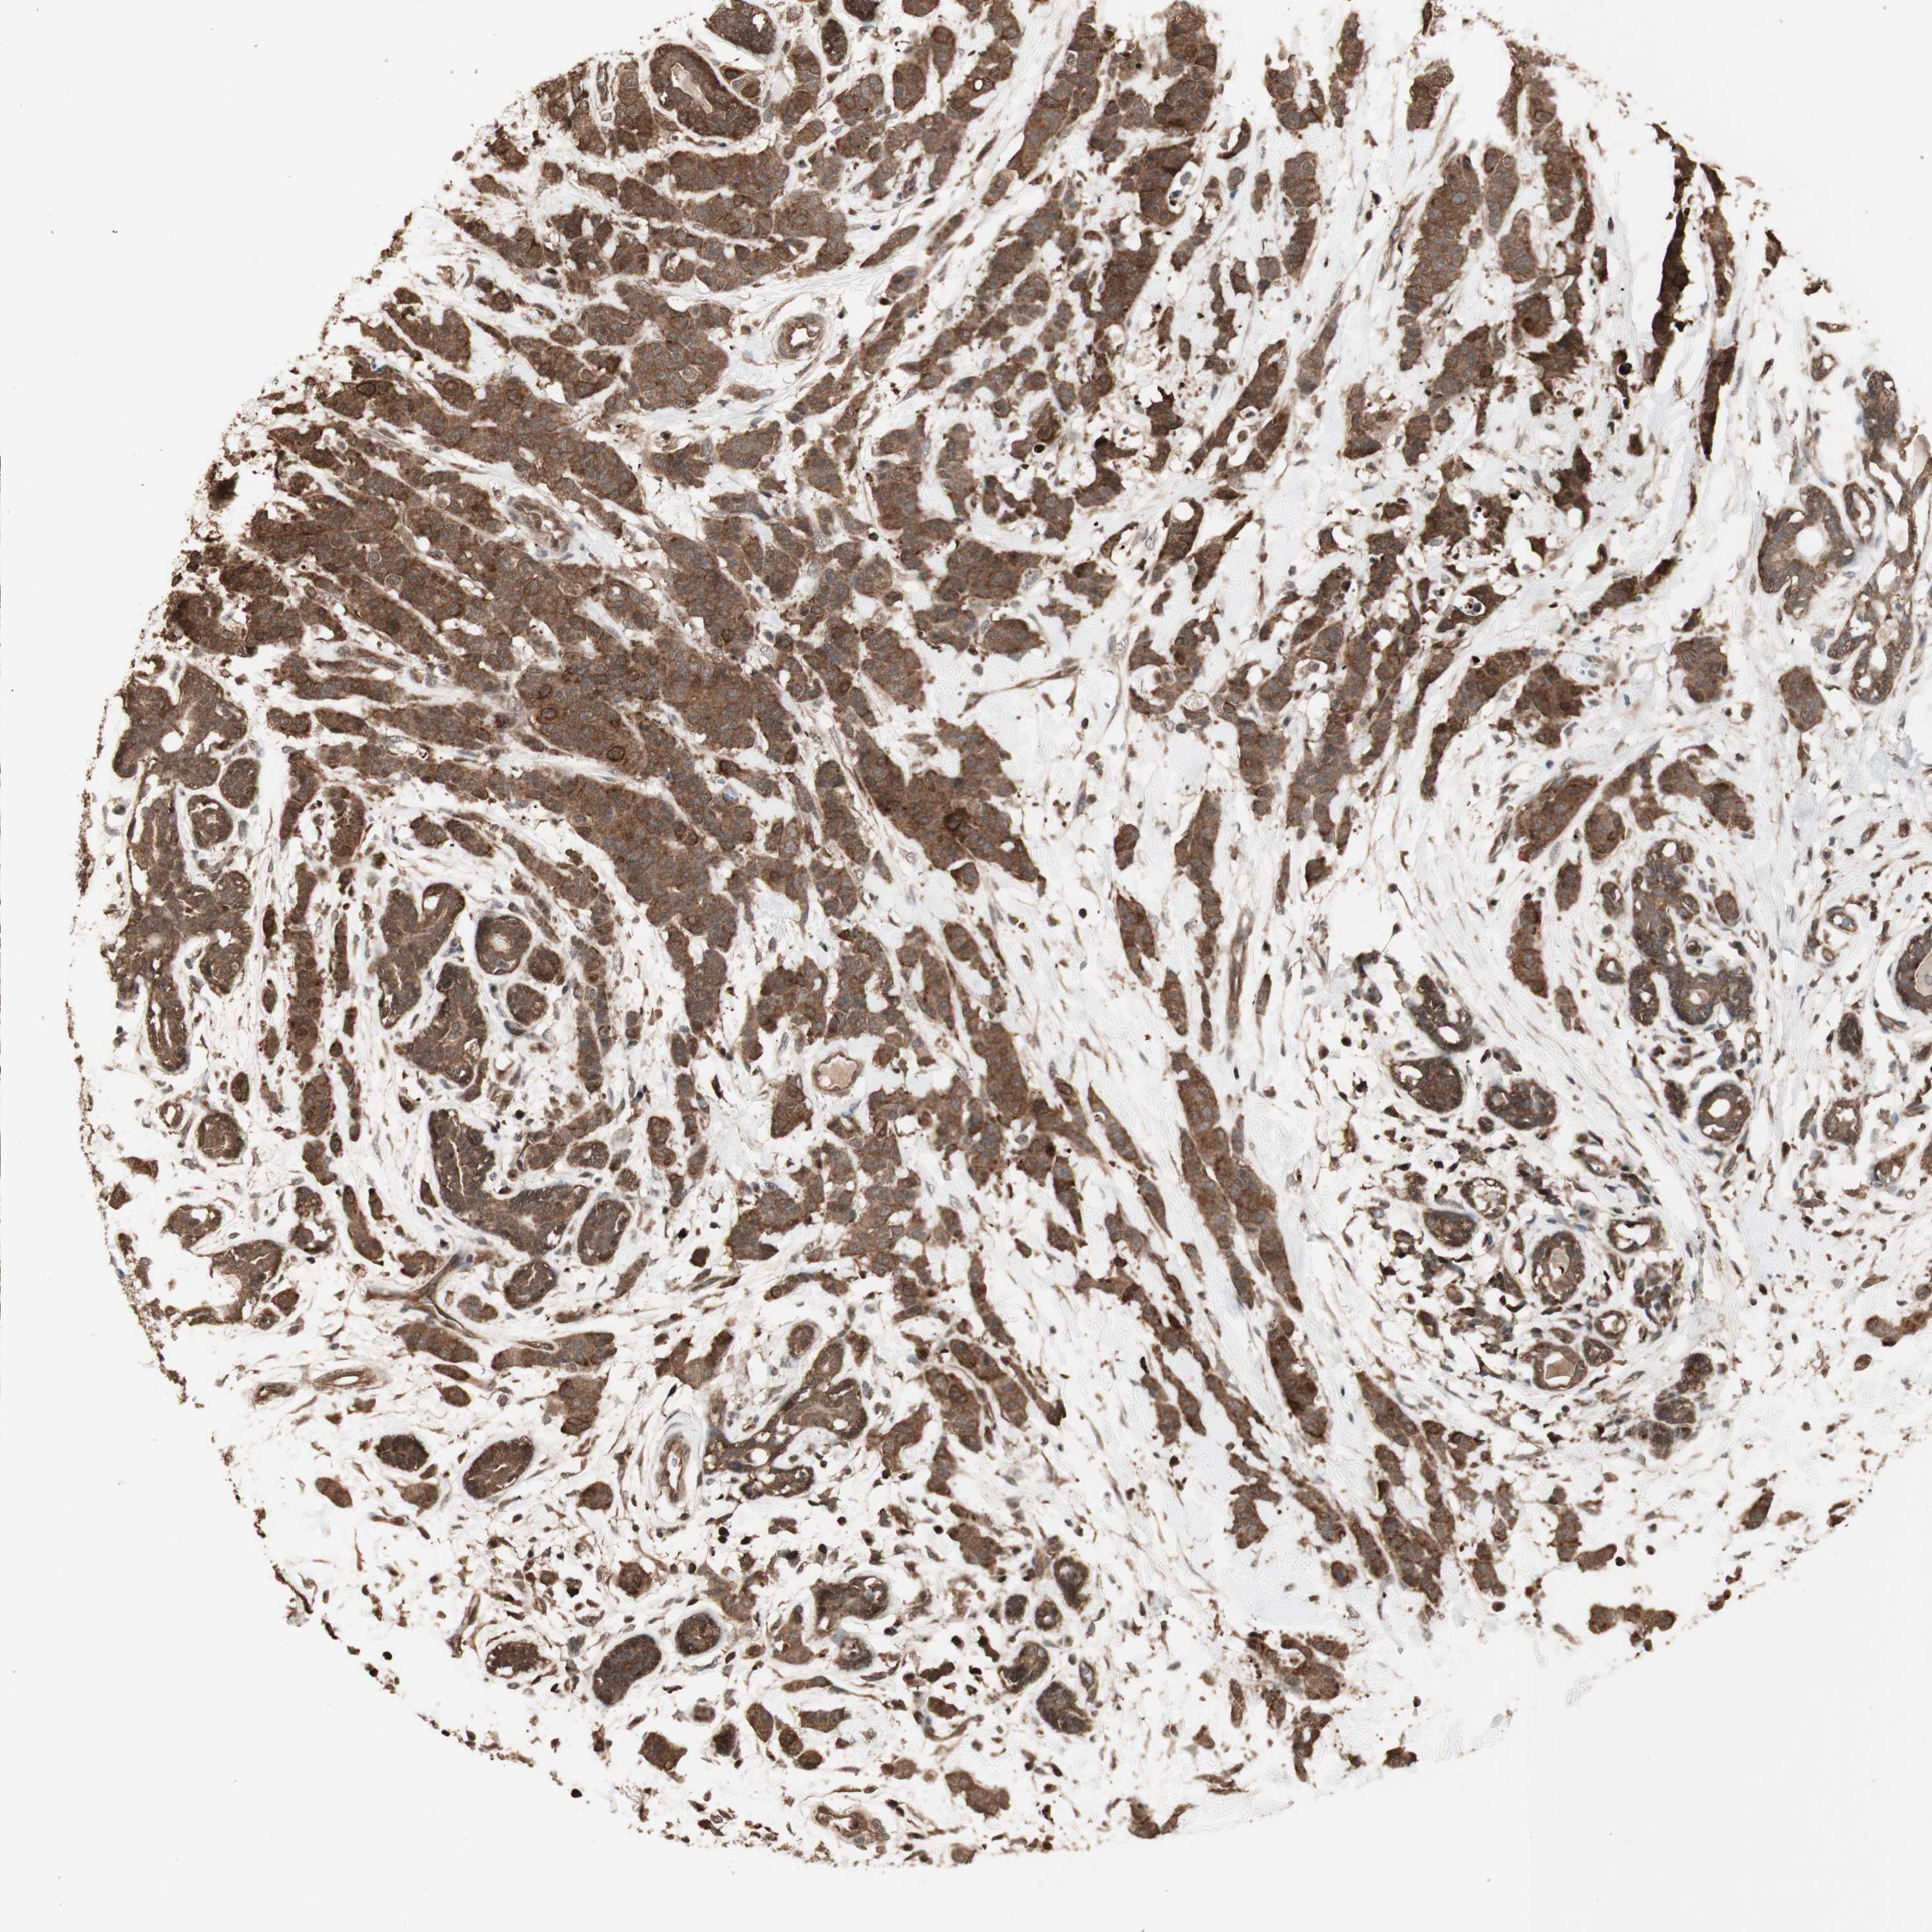

BRCA TCGA BRCA VALIDATION PROTEIN EXPRESSION

ANTIBODIES

AND

VALIDATION